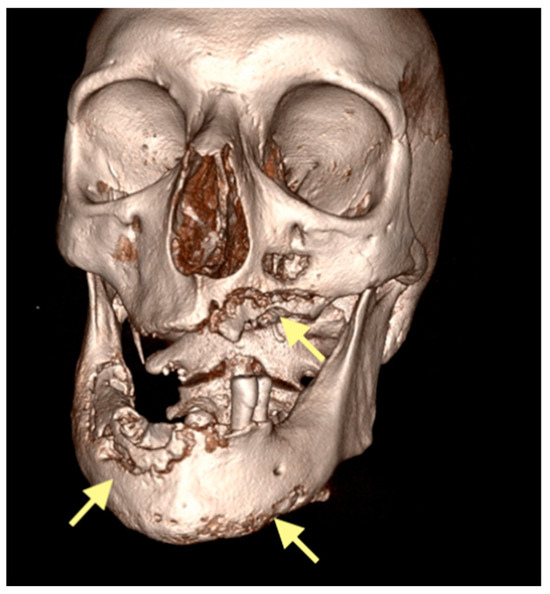

The third patient was a 75-year-old female with osteonecrosis of the mandible and maxilla in the fourth and in the second quadrant (see Figure 7, Figure 8 and Figure 9). The patient had third-stage jaw osteonecrosis. In 2023, the patient was diagnosed with osteonecrosis of the upper and lower jaw caused by antiresorptive therapy (until August 2021, the patient regularly used Zolendronic acid; then, this drug was replaced by the RANKL inhibitor Denosumab). The treatment was periodically complicated by submandibular and submental abscesses. In addition, due to the progression of the underlying disease, constant courses in chemotherapy were administered. The patient underwent three operations, which included sequestrectomy of the jaw with simultaneous use of A-PRF, antrotomy with revision of the maxillary sinus, closure of the oroantral communication, and opening and revision of abscesses of the soft tissues (see Figure 10 and Figure 11)

Figure 7.

CT of the head and facial bones (16 December 2024).

Figure 8.

Figure 9.

Figure 10.

CT of the head and facial bones (19 March 2025) before the last operation (sequestrectomy of the lower and upper jaws; antrotomy performed).